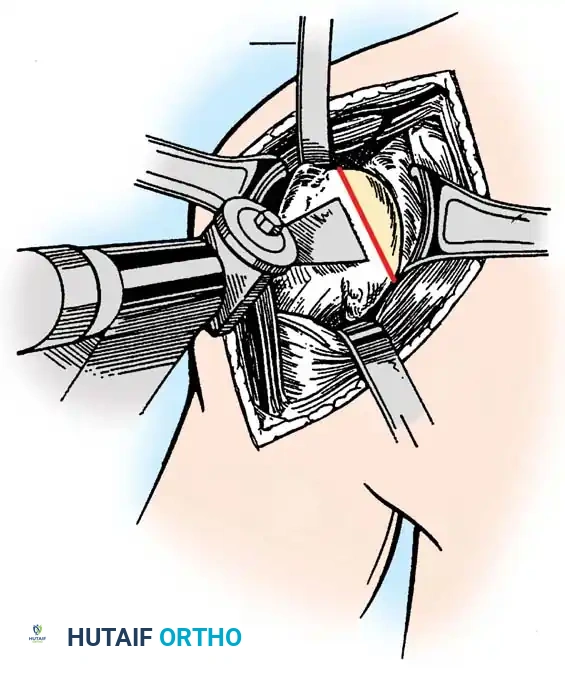

4. Glenoid Preparation

Excellent exposure is critical. Release the inferior capsule completely from the glenoid rim.

* Identify the center point of the glenoid.

* Perform concentric reaming to correct version and create a bleeding bone bed.

* Pitfall: Avoid excessive reaming, which penetrates the dense subchondral bone plate and enters the weaker cancellous vault, leading to catastrophic early subsidence.

Cement the all-polyethylene glenoid component using pulsatile lavage, meticulous drying, and pressurization techniques.